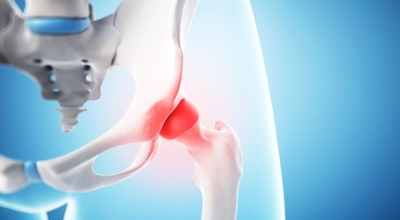

고관절이란 골반을 지탱하는 관절로서 근육과 힘줄로 구성되어 있어요. 학계에서는 고관절을 엉덩이 관절이라고 부르기도 하며 인체의 하중을 지탱하는 아주 중요한 관절입니다. 각별히 고관절은 우리가 정상적으로 서있거나 움직일 수 있게 만들어주며 달리기, 점프, 무거운 무게를 들 때 최대 체중의 2~10배 가량의 하중을 받기 때문에 적절한 관리가 필요합니다. 오늘은 고관절에서 일어날 수 있는 고관절 통증 증상에 관해서 알려드리도록 하겠습니다.

각별히 젊은 남성에게 잘 발생하며 엉덩이와 골반 주위에 뻐근한 통증이 동반되며 정상적인 보행이 되지 않고 절뚝거리는 증상이 나타난다면 대퇴골두 무혈성 괴사일 가능성이 있답니다. 이 증상은 괴사 부위의 골절이 발생되어 고관절 손상으로 이어지면 발생하는 증상으로 아직까지 정확한 원인은 규명하기 힘드나 과음이나 고지혈증, 스테로이드 과남용이 영향을 줄 수 있어요.

나이가 들면 예사로 발생되는 질환 중 한 종류입니다. 관절을 지켜주고 있는 연골의 손상이나 퇴행성 변화로 인해 관절을 이루는 뼈와 인대 등에 손상이 생겨 염증과 통증이 나타나는 질환입니다. 고관절 쪽 연골이 닳게 되면서 망가지게 되고 또 쉽게 없어지지 않는 통증에 시달릴 수 있답니다.